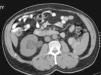

Presentación de caso clínicoSe trata de paciente masculino de 60 años de edad, el cual acude al servicio de urgencias con cuadro de hematuria macroscópica, indolora, no formadora de coágulos. Dentro de su anamnesis refiere nefrectomía radical izquierda por tumor renal, encontrando en el reporte histopatológico tumor de 9cm con necrosis central que invade la cápsula renal. No acudió a sus citas de revisión posterior a la intervención quirúrgica. En la exploración física abdominal, con sitio de cicatriz de lumbotomía izquierda, sin datos de visceromegalias ni puntos doloroso. Los resultados de laboratorio se encuentra: hemoglobina 16g/dl, plaquetas 167,000, creatinina 1mg/dl, BT 1.65mg/dl, BD 0.5mg/dl, BI 1.07mg/dl, fosfatasa alcalina 134 U/l. Se realiza una tomografía simple y contrastada de abdomen y pelvis, observando ausencia quirúrgica del riñón izquierdo, ectasia ureteropiélica derecha con lesión ocupante en el uréter derecho, redondeada, de 2×2cm de diámetro a nivel del cruce con vasos iliacos, con densidad de 10-20 UH y que refuerza en fase contrastada a 50-60 UH (figs. 1 y 2).